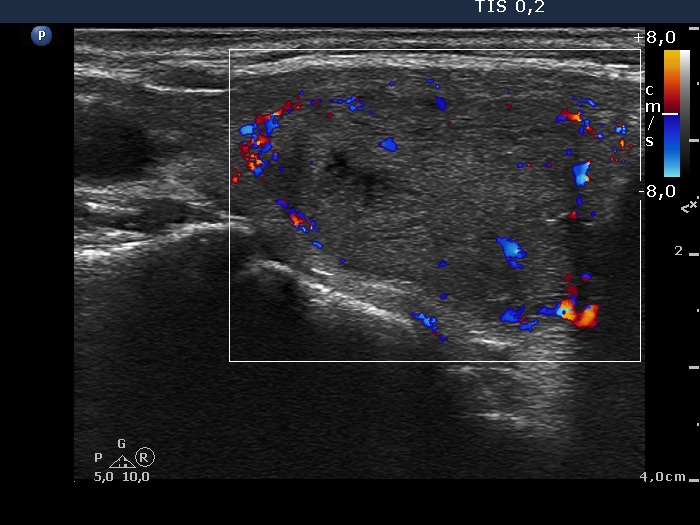

Ultrasonography. The thyroid was echonormal. There was a moderately hypoechogenic nodule in the right lobe. The lesion displayed halo sign and perinodular blood flow.